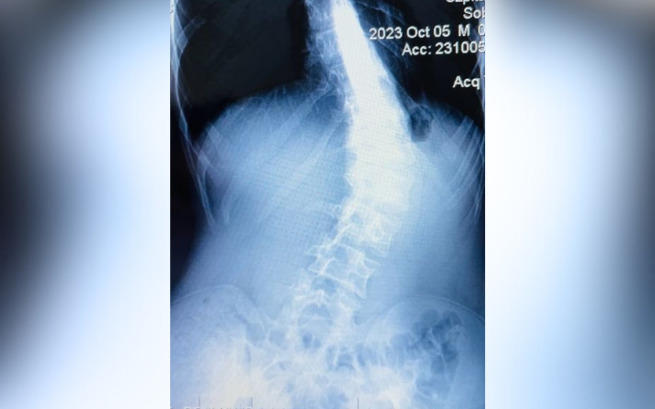

W trybie PILNYM mój syn potrzebuje operacji kręgosłupa❗️Proszę o Twoją pomoc...

Jak wielu z Was wie, Igor przeszedł niedawno operację, która okazała się być wielkim sukcesem.

Jesteśmy teraz po usunięciu szwów, a przed nami ostatnia kontrola pooperacyjna zaplanowana na 28. marca. Chociaż droga do pełnego zdrowia jest jeszcze długa i pełna wyzwań, dzięki Wam poczuliśmy, że nie jesteśmy sami.

Wasza gotowość do pomocy, Wasze serca otwarte na nasze potrzeby, przekroczyły wszystko, czego moglibyśmy się spodziewać. Dziękujemy Wam – za każde słowo, każdą wpłatę, każdy gest wsparcia. Dzięki Wam Igor ma szansę na powrót do normalnego życia, do szkoły, do przyjaciół i do swojej pasji, którą jest pływanie. Teraz przed nami pół roku intensywnej rehabilitacji. Jesteście niesamowici, a Wasza bezinteresowna pomoc i ogrom serc, które dla nas otworzyliście, na zawsze zostaną w naszej pamięci.